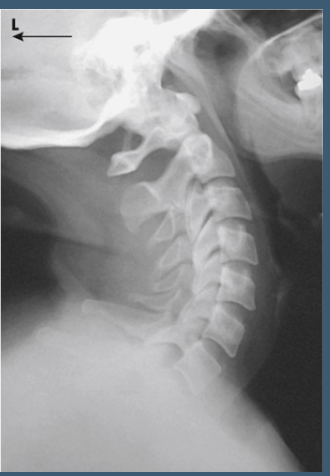

what view is this

hyperextension

What is the CR direction for lateral C-Spine hyperextension?

Horizontal and perpendicular to C4.